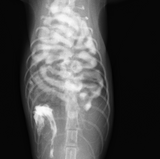

雑種猫 6ヶ月齢くらい メス

主訴

呼吸促迫

画像検査

診断

横隔膜ヘルニア